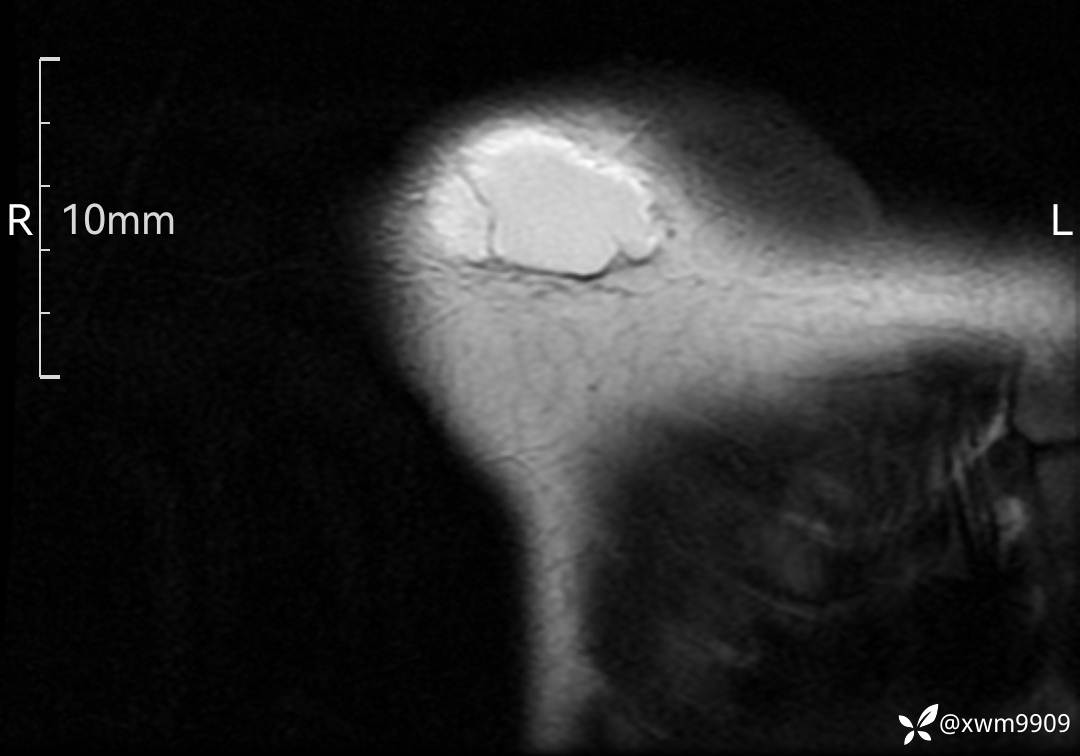

3、查体,右锁下方可及一约5x6Cm肿物,软丶边清丶未见明显发红,肤温不高,压痛明显,不可推动,稍有波动感。其他无特殊。

CT:

2、CT、MR肿块内可见液-液平面,常见有哪些疾病。